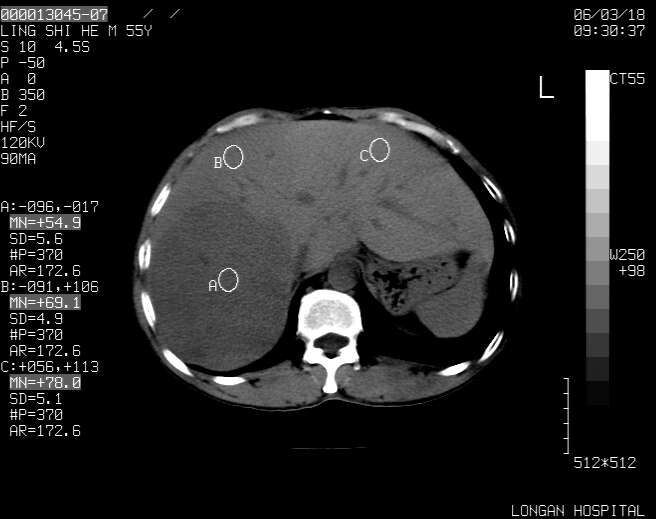

以下是引用guzhongliangddd在2006-3-21 22:13:00的发言:[br]病灶主要位于肝右叶的后份,内见异常血管,门脉主干及右支受侵{提示有癌栓形成},门腔间隙内见增大淋巴结。肝左叶内未见异常。

以下是引用zhuxinli在2006-3-22 1:23:00的发言:[br][br] 病灶主要位于肝右叶的后份,内见异常血管 .门脉右支截断,右叶前段早期强化(考虑动静脉漏),腹膜后肿大淋巴结,病灶逐渐强化,考虑为胆管细胞癌[br]